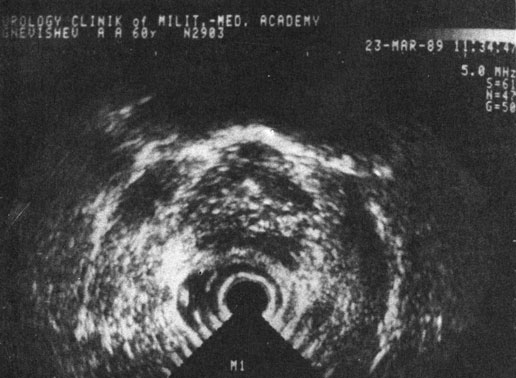

Ультразвуковое сканирование предстательной железы. Основными ультрасонографическими критериями АПЖ являются ее размеры, конфигурация, гомогенность и консистенция, отношение к капсуле. Отсутствие инвазивности и возможность дифференцирования от других заболеваний (РПЖ и ее склероз, простатит) ставят этот метод в одно из первых мест в диагностике данного заболевания.

Рис. 40. Трансректальная горизонтальная ультрасонотомограмма аденомы предстательной железы. утолщена, полулунная, симметричная, размеры ее увеличены. Капсулярное эхо утолщено, непрерывное, внутреннее эхо усилено

Рис. 40. Трансректальная горизонтальная ультрасонотомограмма аденомы предстательной железы.

Обоснованием клинического применения УЗИ послужили фундаментальные эхоморфологические работы ряда авторов [Peneau М. et al., 1985; Frentzei-Beyme В., Ledwa D., 1986; Pencert A., Ristan U., 1986, и др.]. Авторы установили корреляцию результатов морфологических исследований и ультразвуковых признаков АПЖ, используя биопсийный и секционный материал.

А. Ф. Цыб и соавт. (1987) и др. отмечают, что предстательная железа в норме имеет форму неправильного треугольника с соотношением основания и высоты 5 : 3, с четкими контурами, эхооднородную, имеющую мелкогранулярную структуру. Капсула железы повышенной эхоплотности четко разграничена с клеточным пространством перед стенкой прямой кишки шириной в 4-5 мм, пониженной эхоплотности. Для АПЖ характерны большие размеры, овальная форма, симметричность, иногда намечающийся внутрипузырный узел, однородная внутренняя эхоструктура. Капсула - четко определяемая, гладкая (рис. 40), что отличает ее от прерывистой линии при РПЖ III-IV стадий. При этом отмечается неоднородная эхоструктура, что, однако, может иметь место и при диффузной гиперплазии предстательной железы [Frentzei-Beyme В., Ledwa D., 1986]. При дифференцировании АПЖ и РПЖ следует учитывать характерную локализацию неоднородных эхоструктур при раке в каудальной зоне и возможность их обнаружения за пределами капсулы. При хроническом простатите выявляются симметричные гиперэхогенные очаги. Камни предстательной железы характеризуются интенсивными, локально ограниченными, эхологически плотными участками, иногда с акустической тенью.

В последнее время с появлением ультразвуковых аппаратов второго поколения нашли применение 4 методики ультразвуковой визуализации: надлобковая, поперечная трансуретральная, поперечная и продольная трансректальная. Сторонники трансректального УЗИ [Fritzsche P. et al., 1983; Burks D. et al., 1986; Wiegand S., Weidner W., 1986, и др.] объясняют это увеличивающимися возможностями дифференциальной диагностики с РПЖ, простатитом и др. Однако это несколько уменьшает неинвазивность метода, так как требует подготовки кишечника и навыков введения ректального датчика в сигмовидную кишку [Okafor P. et al., 1983]. В то же время улучшившиеся технические возможности увеличили информативность совершенно неинвазивных методик. P. Walz и соавт. (1983), О. Utzmann и соавт. (1985), G. Galdellin и соавт. (1986), W. Hubrich (1986) придают большое значение надлобковому доступу при проведении УЗИ. Наши наблюдения дают основание считать, что надлобковое УЗИ является вполне информативным при АПЖ, если не возникает необходимость проведения дифференциальной диагностики с другими заболеваниями, особенно РПЖ. УЗИ являются также необходимыми при проведении чрескутанных эндовезикальных операций при заболеваниях, обусловленных АПЖ для динамического контроля.